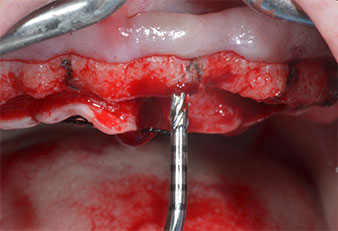

Ein flammenförmiges, diamantiertes piezochirurgisches Instrument (Piezomed I1) wurde verwendet, um die Implantatpositionen zu markieren und die Pilotpräparationen durchzuführen (Abb. 3). Dabei wurde darauf geachtet, eine Auf- und Abbewegung mit reduzierter Leistung, voller Spülung und niedrigem Druck (unter 300 g) anzuwenden. Als Nächstes wurde ein Pilotinstrument (Piezomed I2A/I2P) zur initialen Erweiterung der Implantatlager auf einen Durchmesser von 2 mm verwendet (Abb. 4), gefolgt von einem 3-mm-Instrument (Abb. 5).